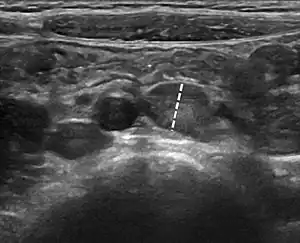

| Abdominal ultrasound showing large mesenteric lymph nodes in a 6-year-old with mesenteric lymphadenitis. The largest lymph node (dashed line) measurement was 9 mm.[1] | |